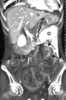

Mesenteric metastasis